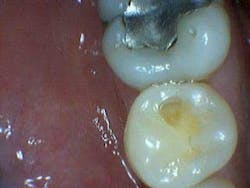

In the aforementioned case, the reading on the occlusal surface was a 46 (see Figs. 3 through 8 below). Look at what was underneath. Surprised? I often wonder how many times per day lesions like this are going undiagnosed.